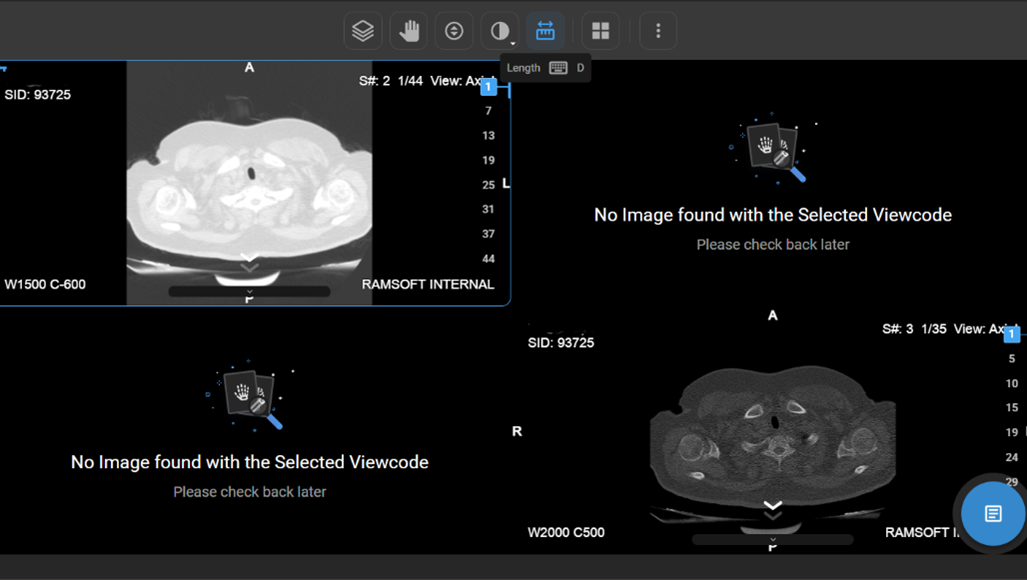

How Do I Measure Length?

- Usage: Measure distance between two points.

- Hotkey: Press D.

- Clinical Utility: Helps measure anatomical structures or lesion sizes.

- Locate the Length tool on the wheel and click on it to calculate the distance between two points on the image, useful for measuring anatomical structures.

How Do I Change the Viewport Layout?

-

Open Layout Selector from the toolbar.

a. A 3×3 grid appears, with the current layout highlighted.

Adjust Viewports:

a. Drag to increase/decrease viewports (up to 8×8 grid per monitor).

Apply Hanging Protocols:

a. Available in a drawer beside the selector.

Select one to apply it:

a. Single Monitor: Affects only that monitor.

b. Multi-Monitor: Applies to all monitors.

How Do I View Multiple Images or Series in Different Layouts?

- If there are multiple images or a series of images, you can customise the display layout to enhance your viewing experience.

- Locate and click on the Change Layout icon in the image viewer toolbar at the top of the screen.

- Select the desired layout format to switch between a single-frame view and a multi-frame display for comparing multiple images simultaneously.